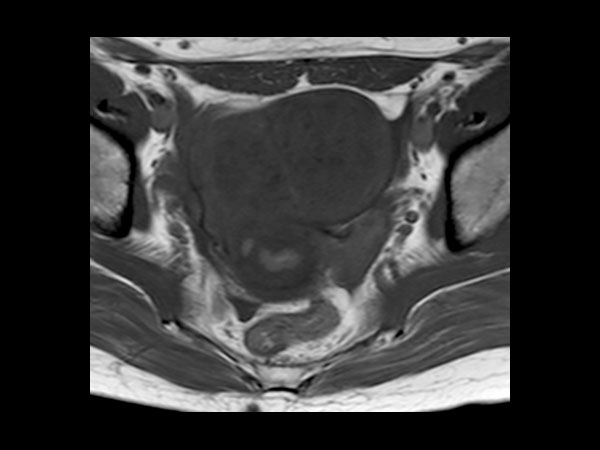

Female Pelvis

Toyonaka Hospital, Japan

• Clinical Application